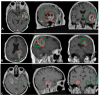

Figures